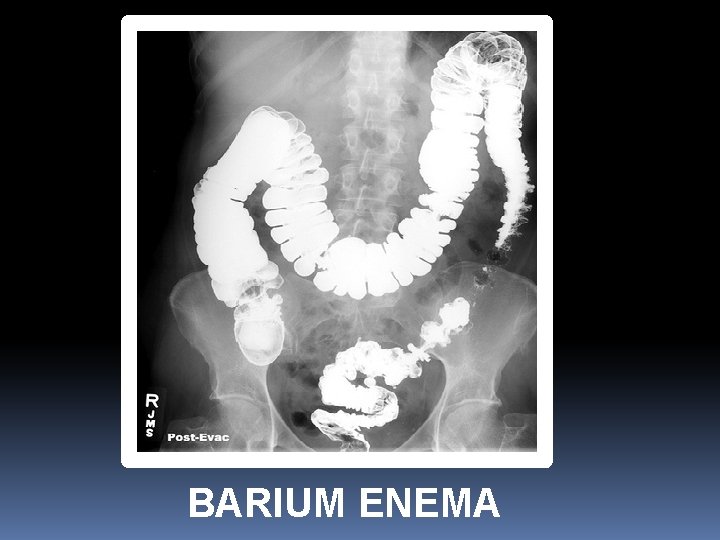

BARIUM ENEMA

What is abnormal in this barium enema?

Colon mass/malignancy (Apple core appearance)